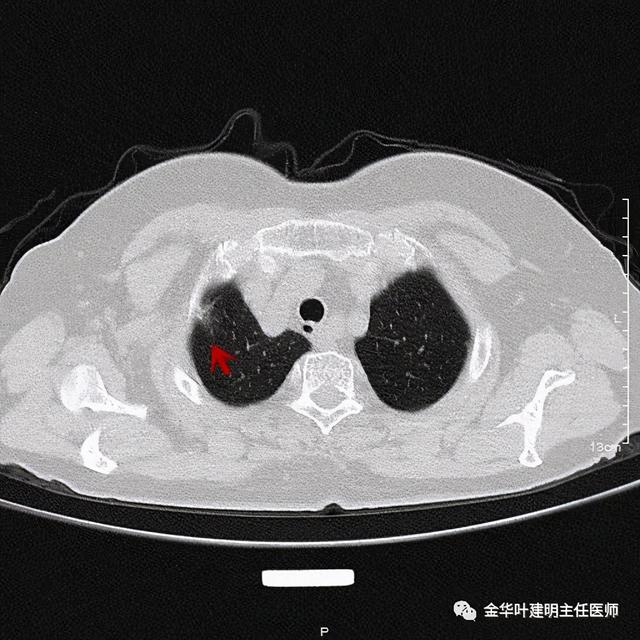

靶扫描更清楚显示瘤肺边界较清、分叶及密度不均杂乱 , 并有少许胸膜牵拉凹陷 , 当然考虑是肺癌 , 而且应该是浸润性腺癌了 。 其长径达2.5厘米!靶扫描还发现了平扫没被注意到的另一个病灶:

文章插图